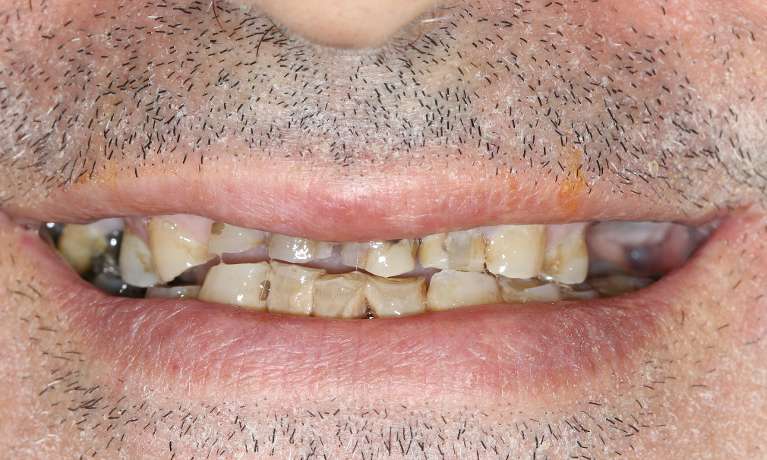

This patient arrived with several missing and decayed teeth, impacting both their oral health and confidence. Through the innovative All-on-4 dental implant procedure, they received a complete, beautiful and functional new smile.